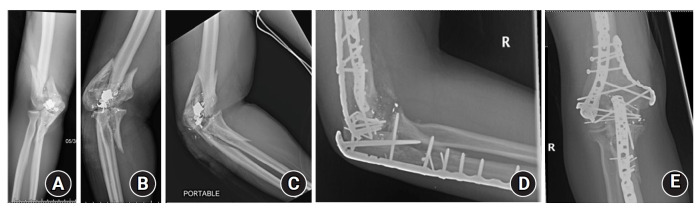

Results: Twenty-four patients were identified. All patients received prophylactic antibiotics upon admission and underwent urgent surgical debridement. Open reduction and internal fixation (ORIF) was performed with initial debridement in 22 of 24 patients. Seven patients sustained distal humerus fractures, 10 patients sustained isolated proximal ulna or proximal radius fractures, and seven had combined fracture patterns. Eleven patients presented with nerve palsy, and two had transected nerves. Two patients had vascular injury requiring repair. One patient required a temporary elbow-spanning external fixator and underwent staged debridement followed by ORIF. One patient with a grade IIIC fracture developed a deep infection that precluded ORIF. One patient required revision ORIF due to fracture displacement.

Abstract Image